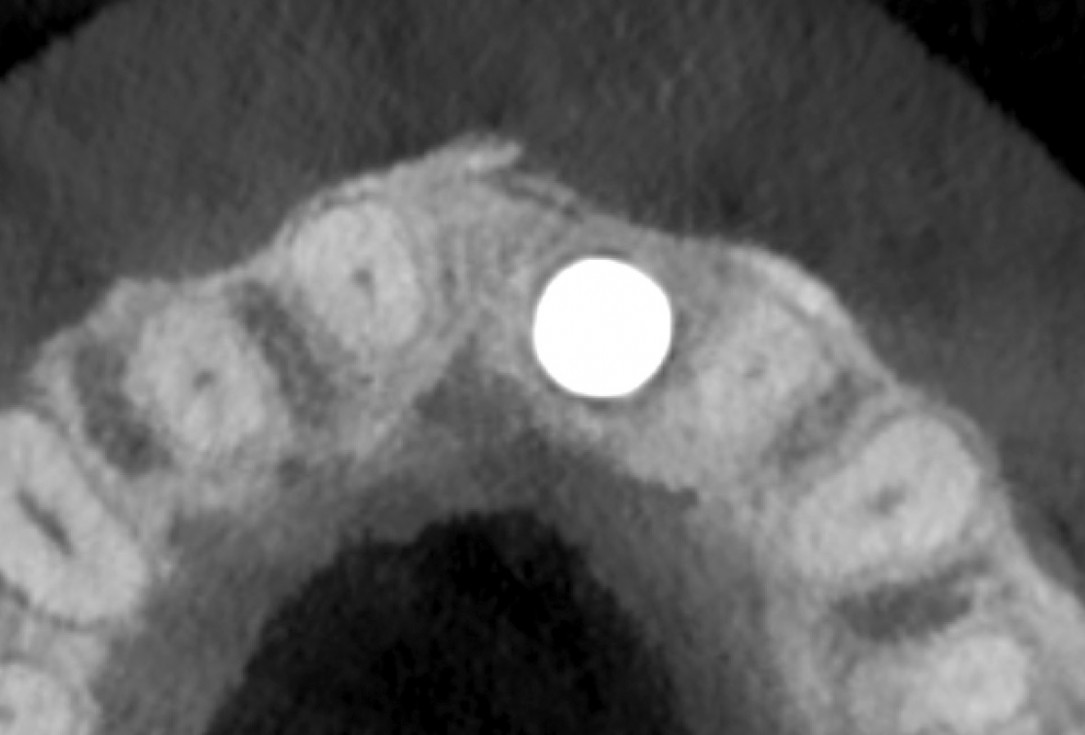

33/35 - 5 y post op CBCT - Axial view at the coronal 2mm levelBlock grafting in the aesthetic zone with maxgraft®, Jason® membrane and cerabone® - Dres. H. Maghaireh and V. Ivancheva